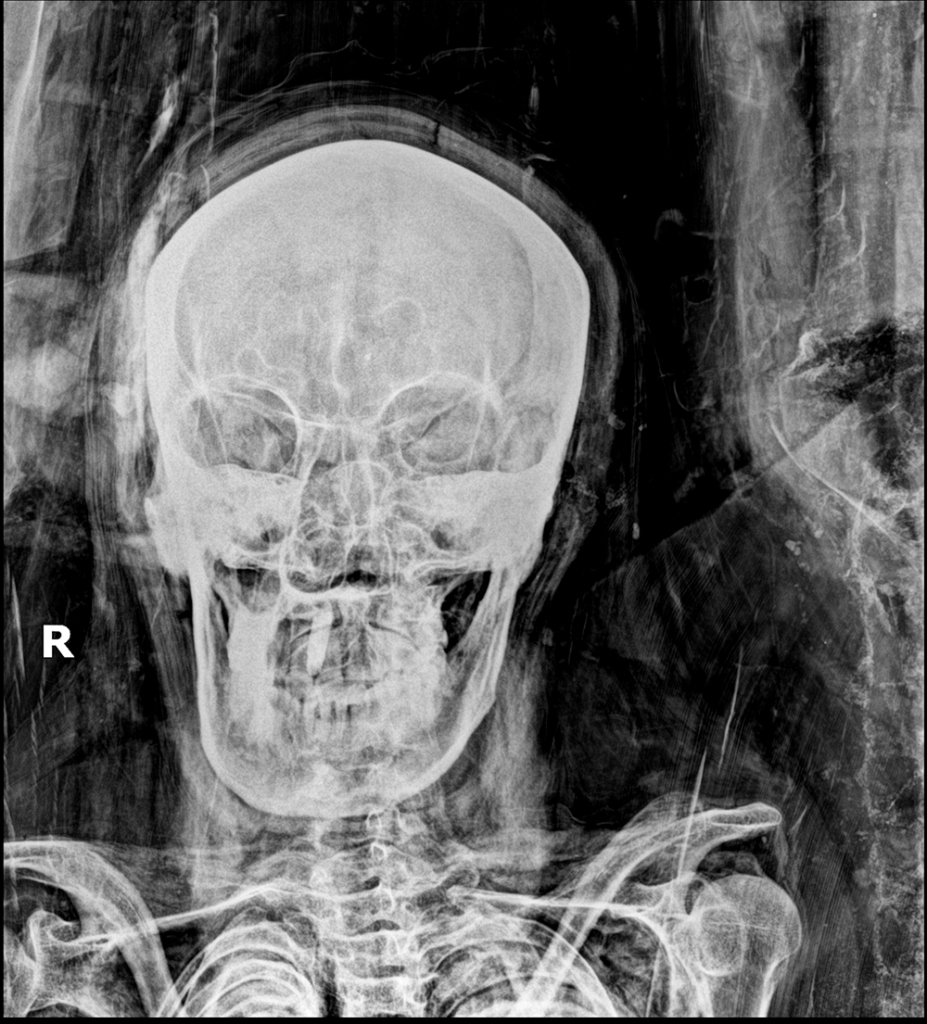

Unfortunately, only a minority of patients have this typical COVID-19 pattern. In most patients, the disease is located more diffusely or elsewhere. Consolidation may be present initially with more severe illness or duration (Fig. 2).